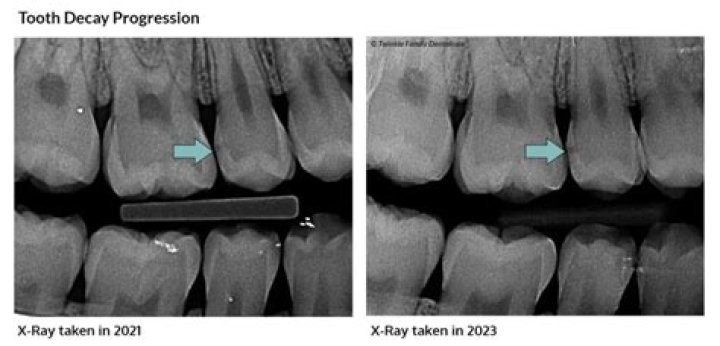

If the deepest layers of the pulp become infected, it may be too late to save the tooth. In addition, if a large portion of the tooth is lost and a crown ...